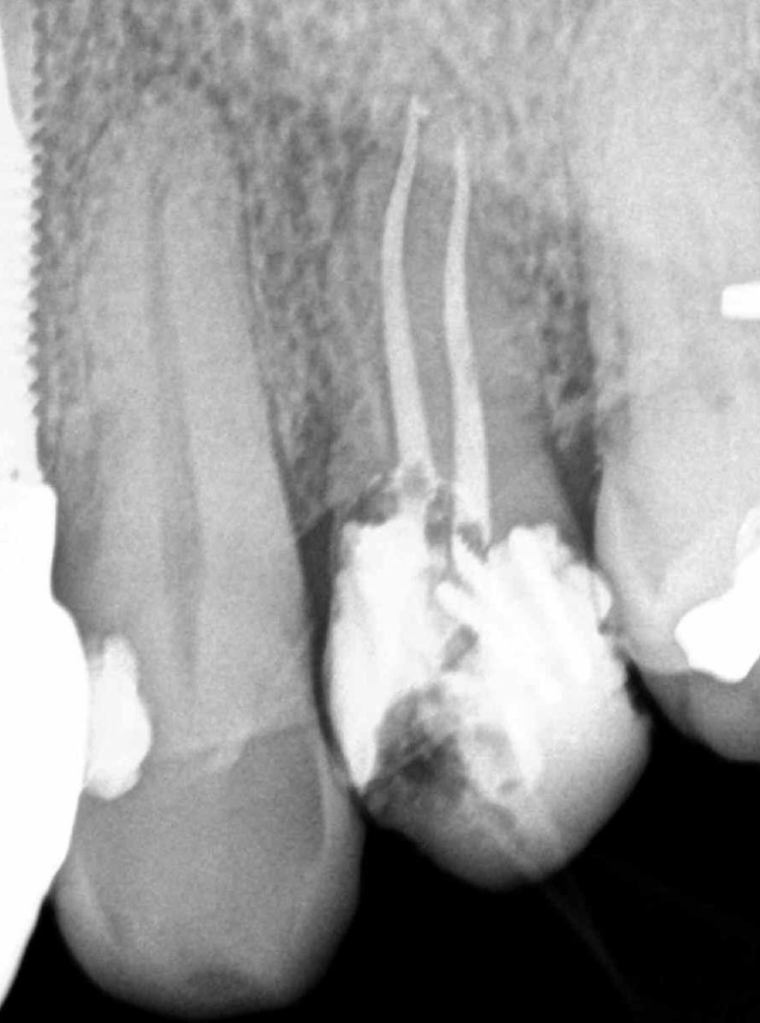

Premolar calcificado lesion